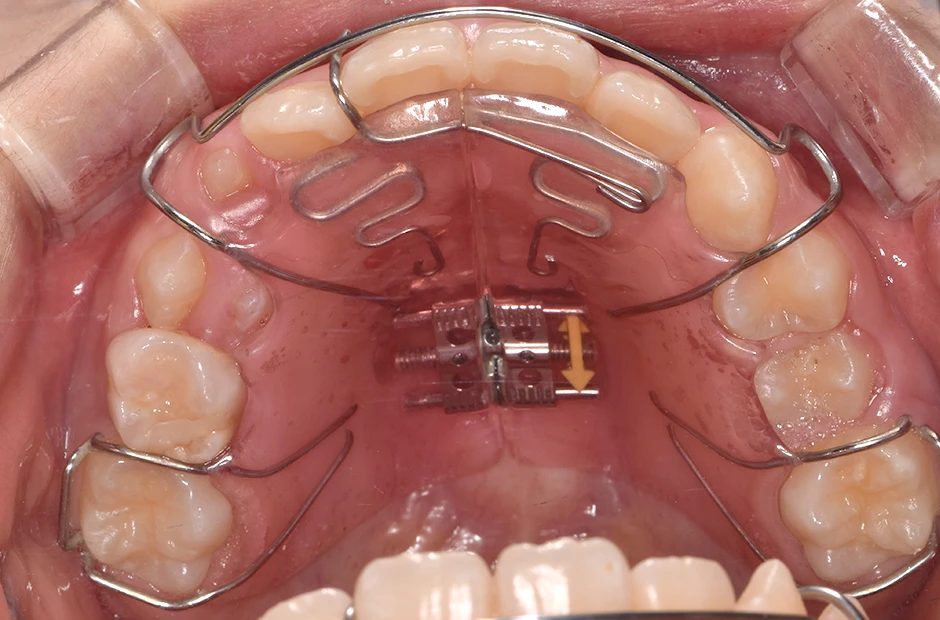

急速拡大装置

上顎の幅を短期間で拡げる矯正装置です。金属のバンドとワイヤー、ネジで構成されており、上顎の天井部分に装着します。装置中央にあるネジを回すことで顎骨に負荷をかけ、上顎の骨全体を短期間で拡げていきます。歯を並べるためにより多くのスペースが必要な場合に使用します。